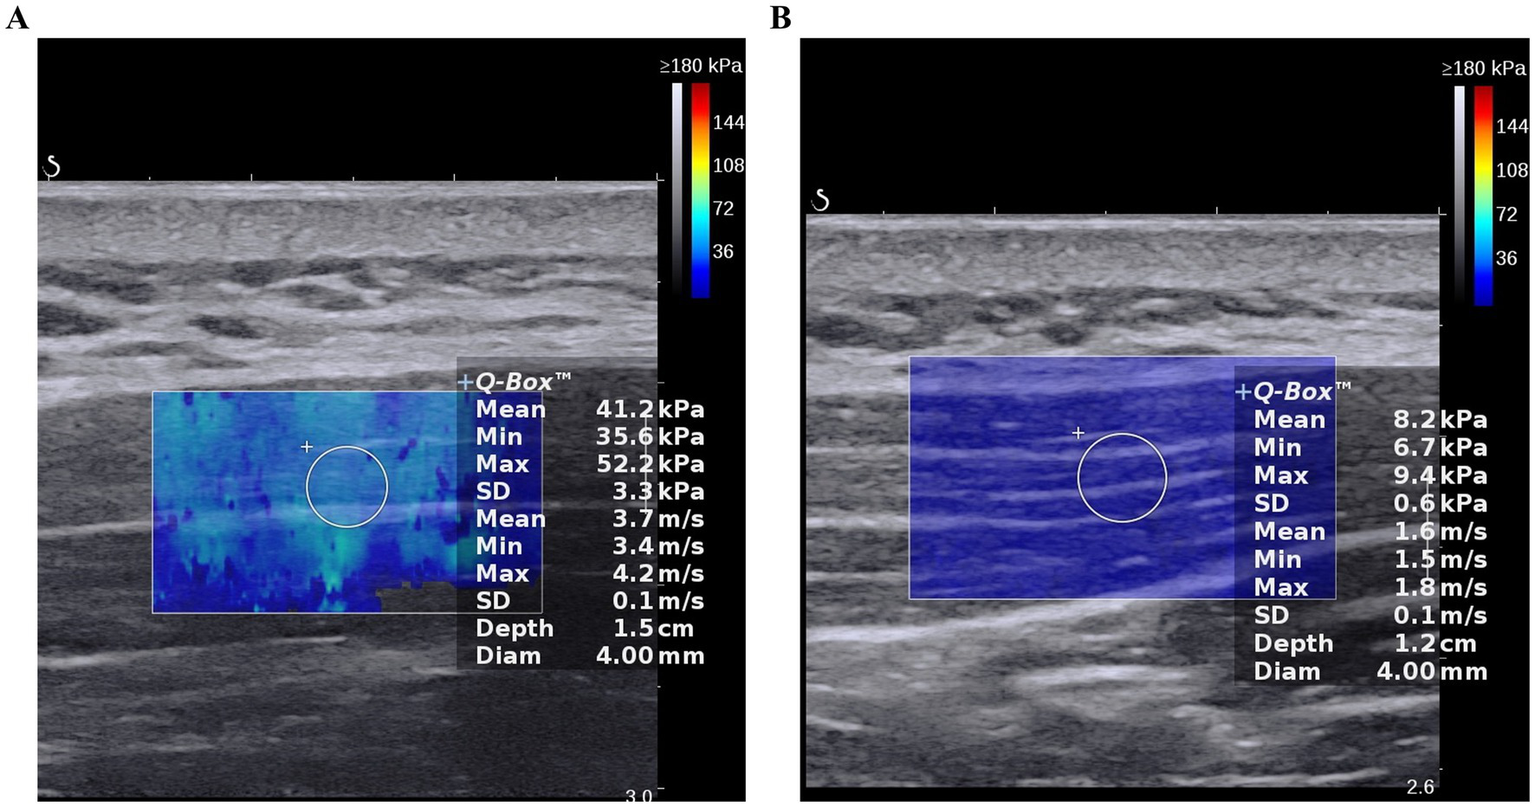

The median difference between the FSN group and the FN group at after treatment, along with their respective 95% confidence intervals, were 2.167 (0.667–3.367). Before treatment, there was no statistically significant difference in the SWE elastic modulus values of the upper trapezius muscle between the two groups (p > 0.05), thus indicating comparability. After treatment, the SWE elastic modulus values of the upper trapezius muscle in the FSN group decreased significantly compared with that before treatment (p < 0.05, Figures 3A,B); there was no such reduction in the FN group (p > 0.05) (Table 6).

Figure 3

The SWE elastic modulus value prior to treatment and following treatment in Fu’s Subcutaneous Needling (FSN) Group; (A). Prior to treatment; (B). Following treatment.